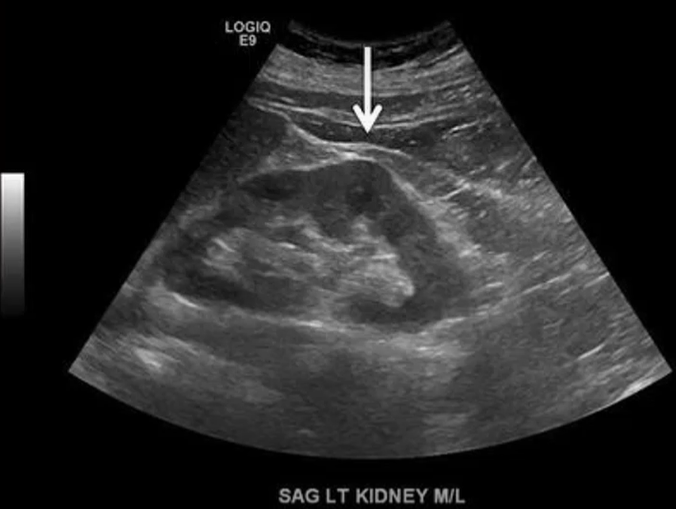

A dromedary hump is usually on the ___ kidney. And the echogenicity is the ___ as the rest of the renal ___.

left, same, parenchyma

What normal variant of the kidney is a bulge of the renal cortex on the lateral surface of the kidney thought to be a result of pressure on the developing fetal kidney from the spleen?

Dromedary hump